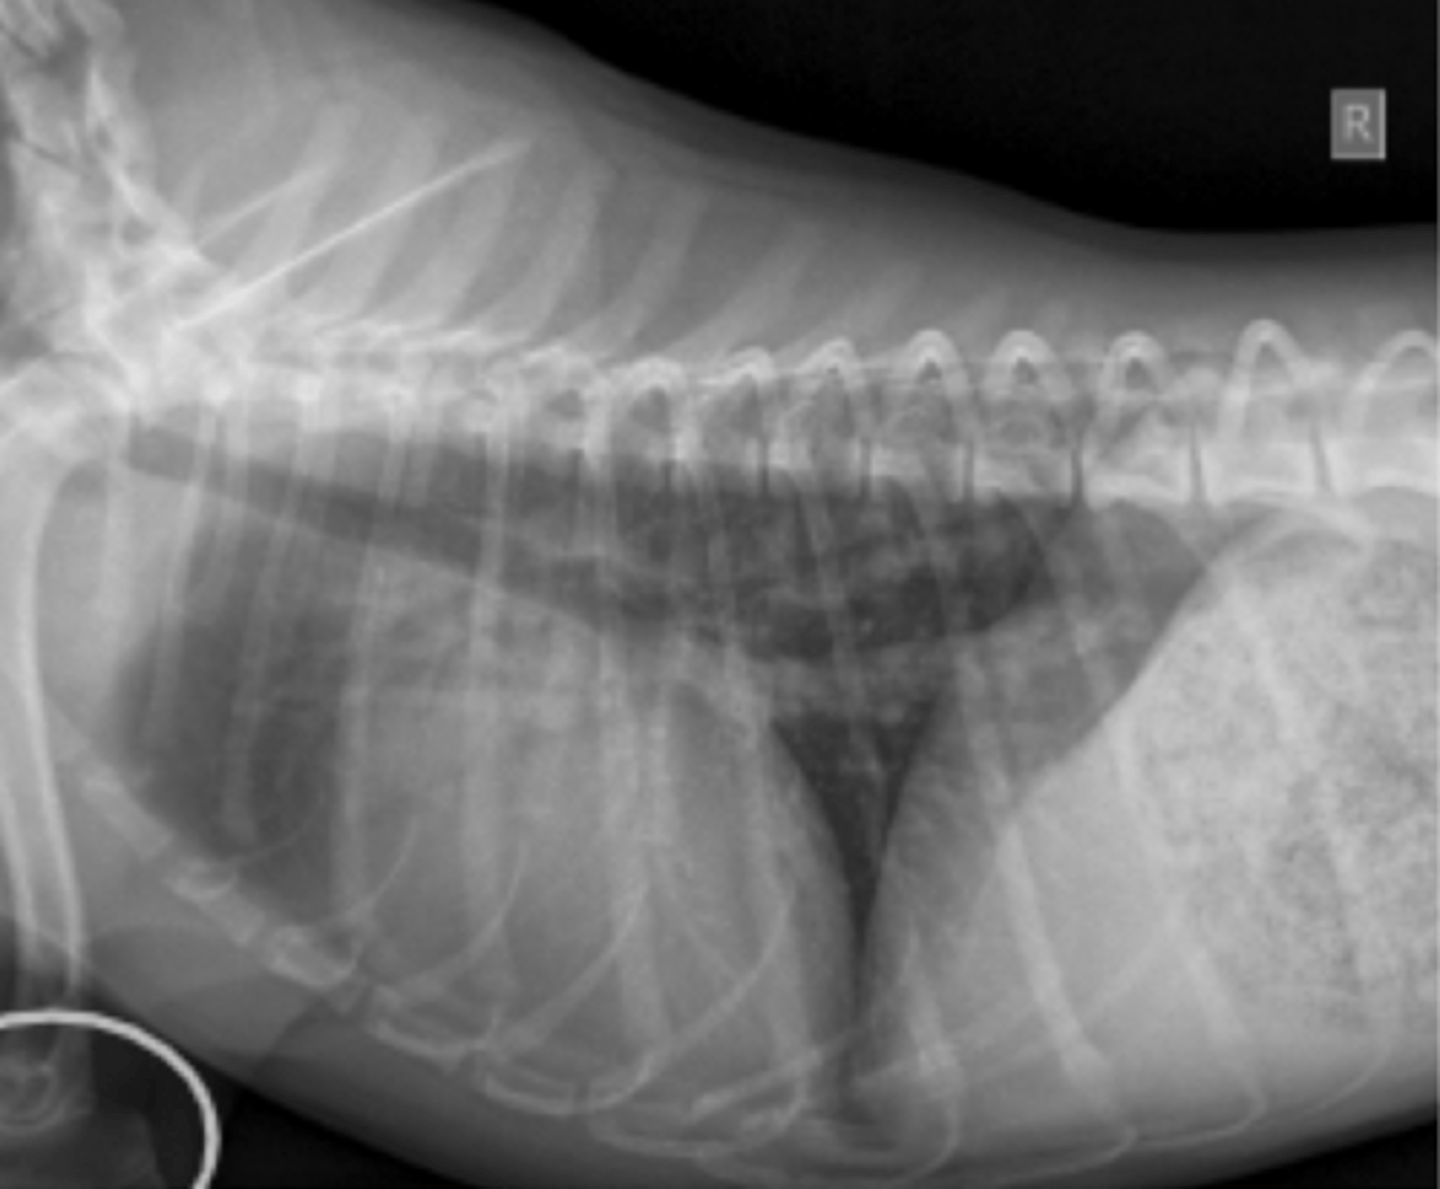

microcardias

(silueta separado de la diafragma)

patología:

(silueta separado del esternón)